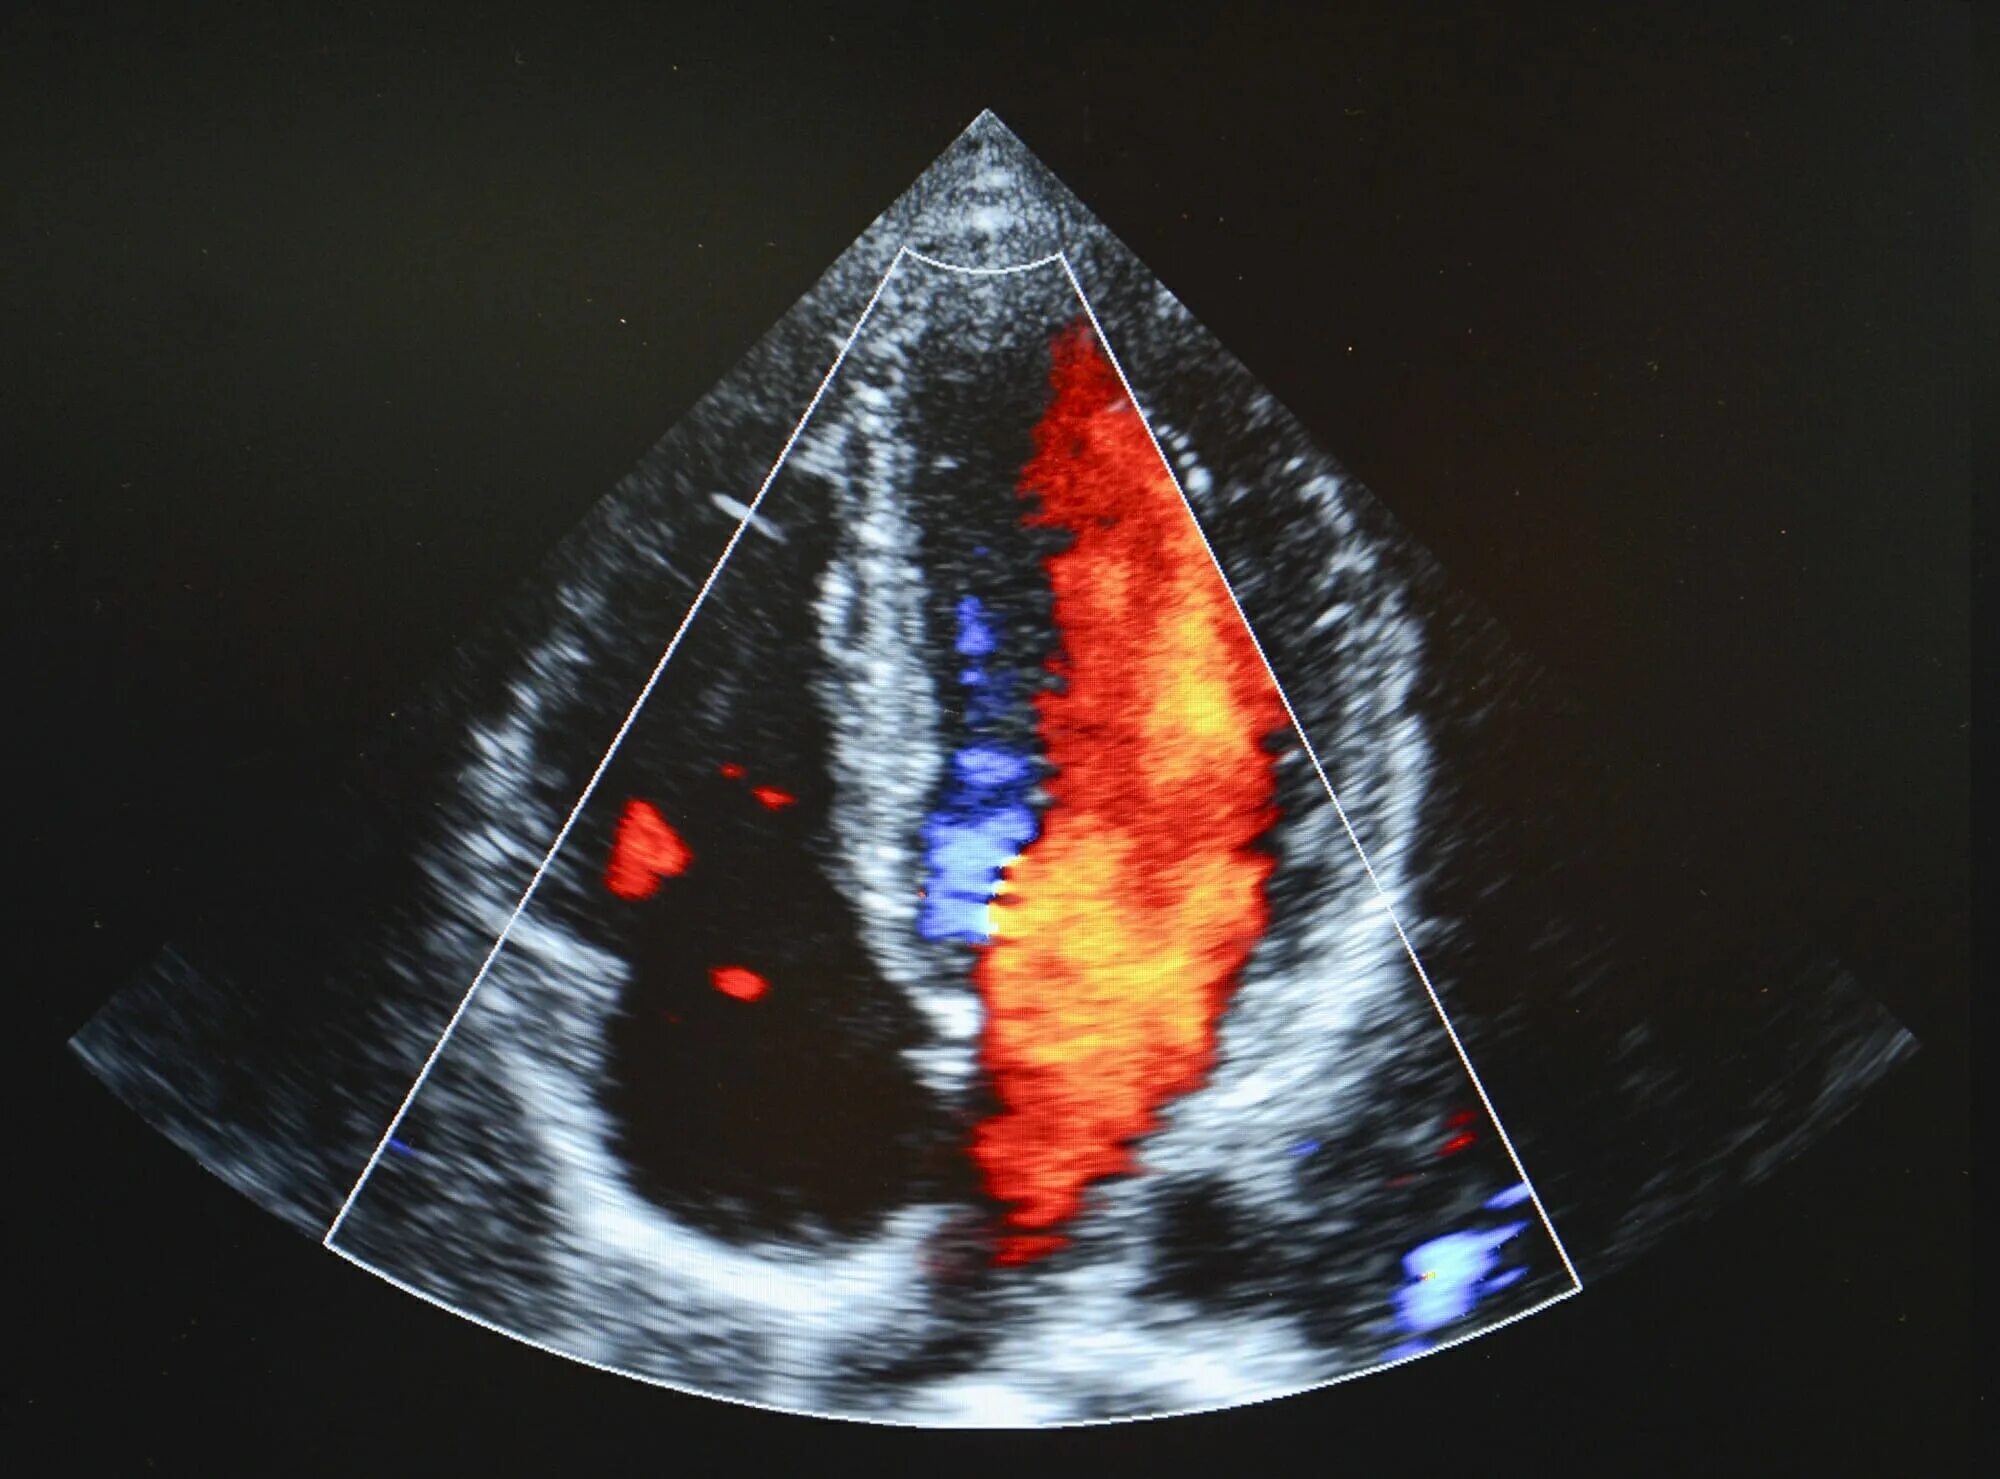

Мпп у новорожденного